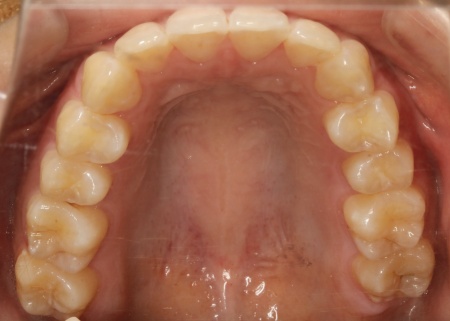

20代女性 乱れた上下の歯並びをハイブリッド矯正で改善した症例

拝見したところ、上下の歯はデコボコに生えている状態でした。

歯並びがある程度正しい位置に並んだら、マウスピース矯正で微調整を行いました。

歯の移動が完了したあとは定期的に経過を確認しながら、後戻りを防ぐためのリテーナー(保定装置)を継続して使用いただき、治療を終了しました。